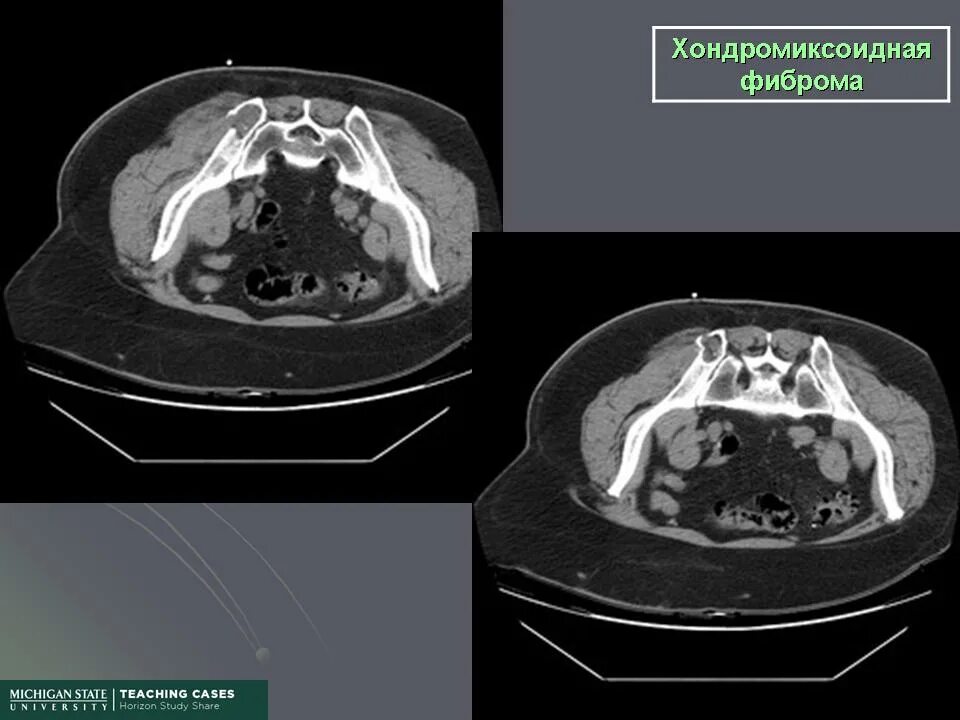

Фиброма кт